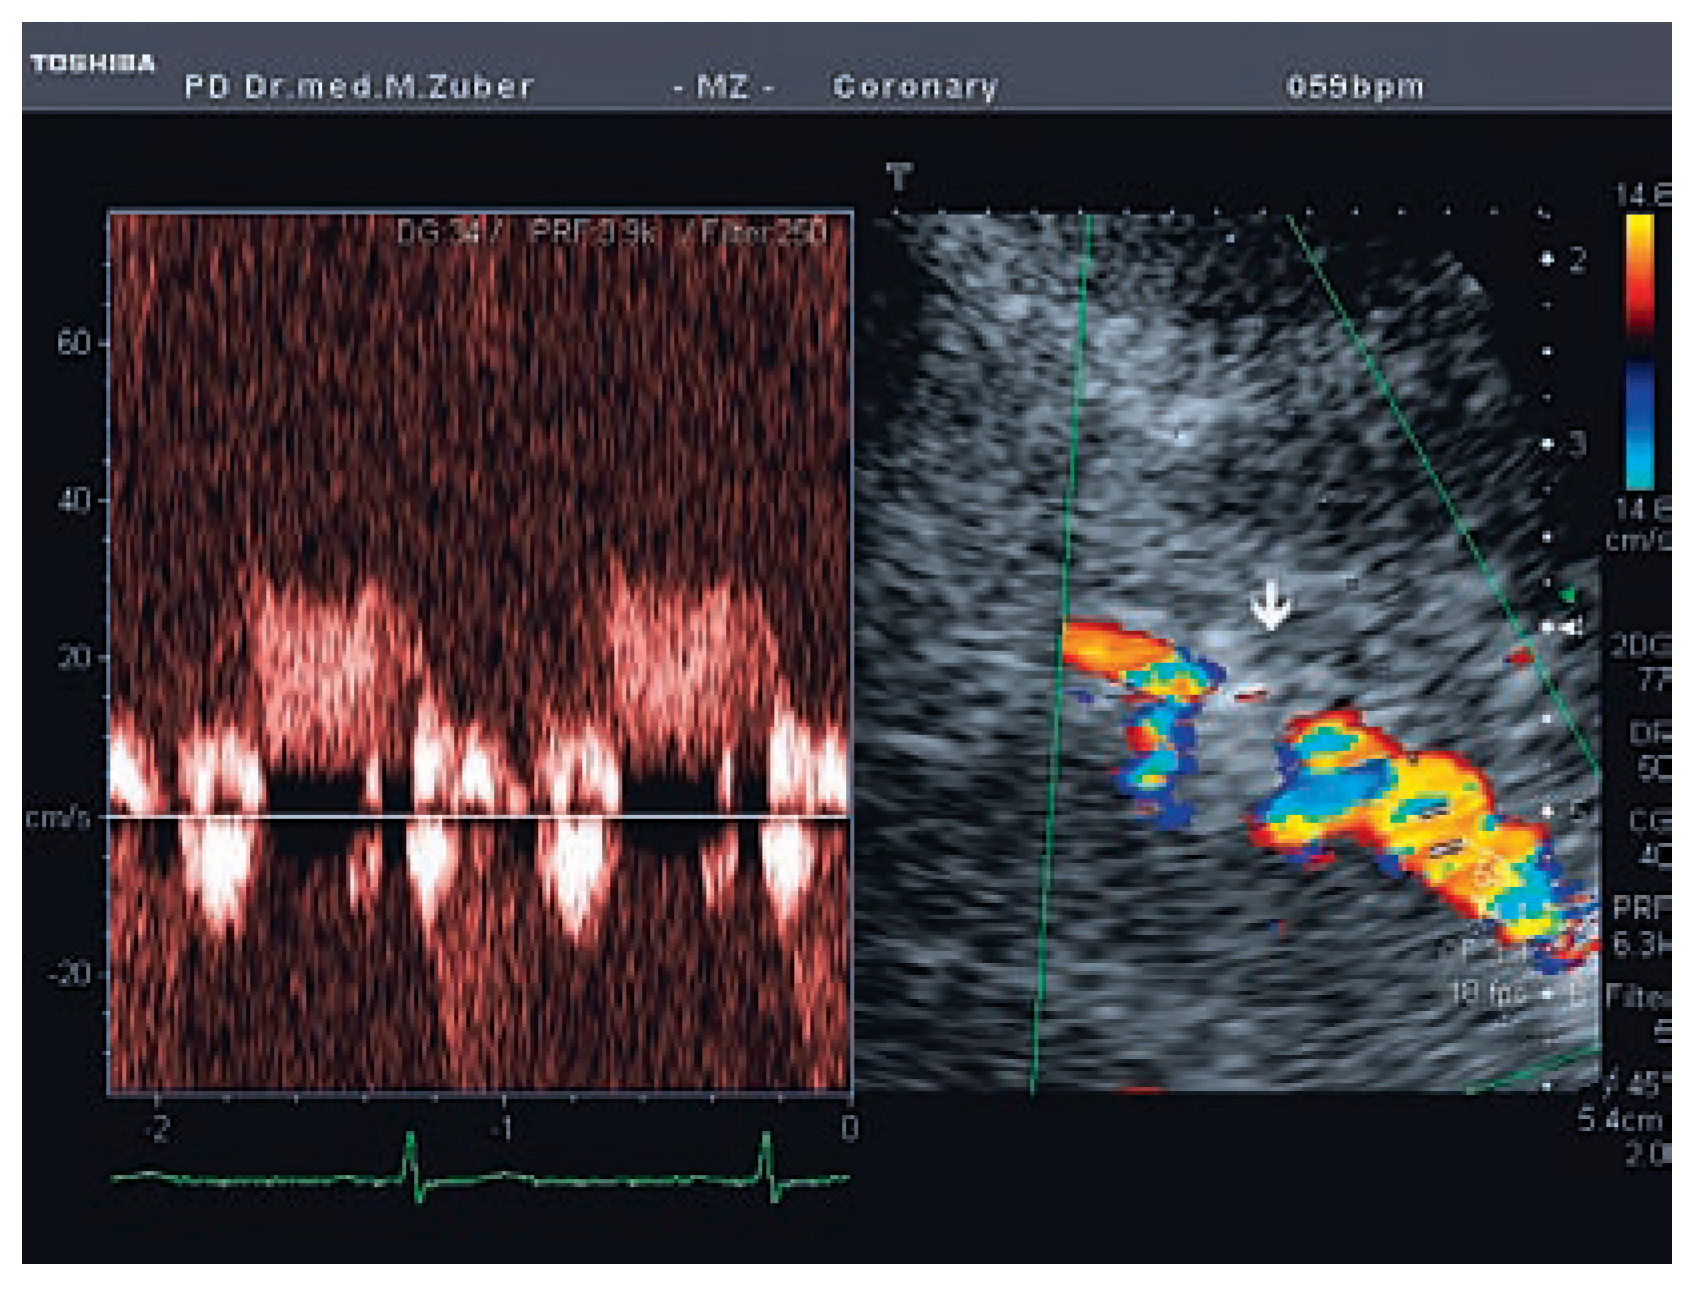

Koronarstenose Und Transthorakale Farbdopplerechokardiographie

Fallbeschreibung